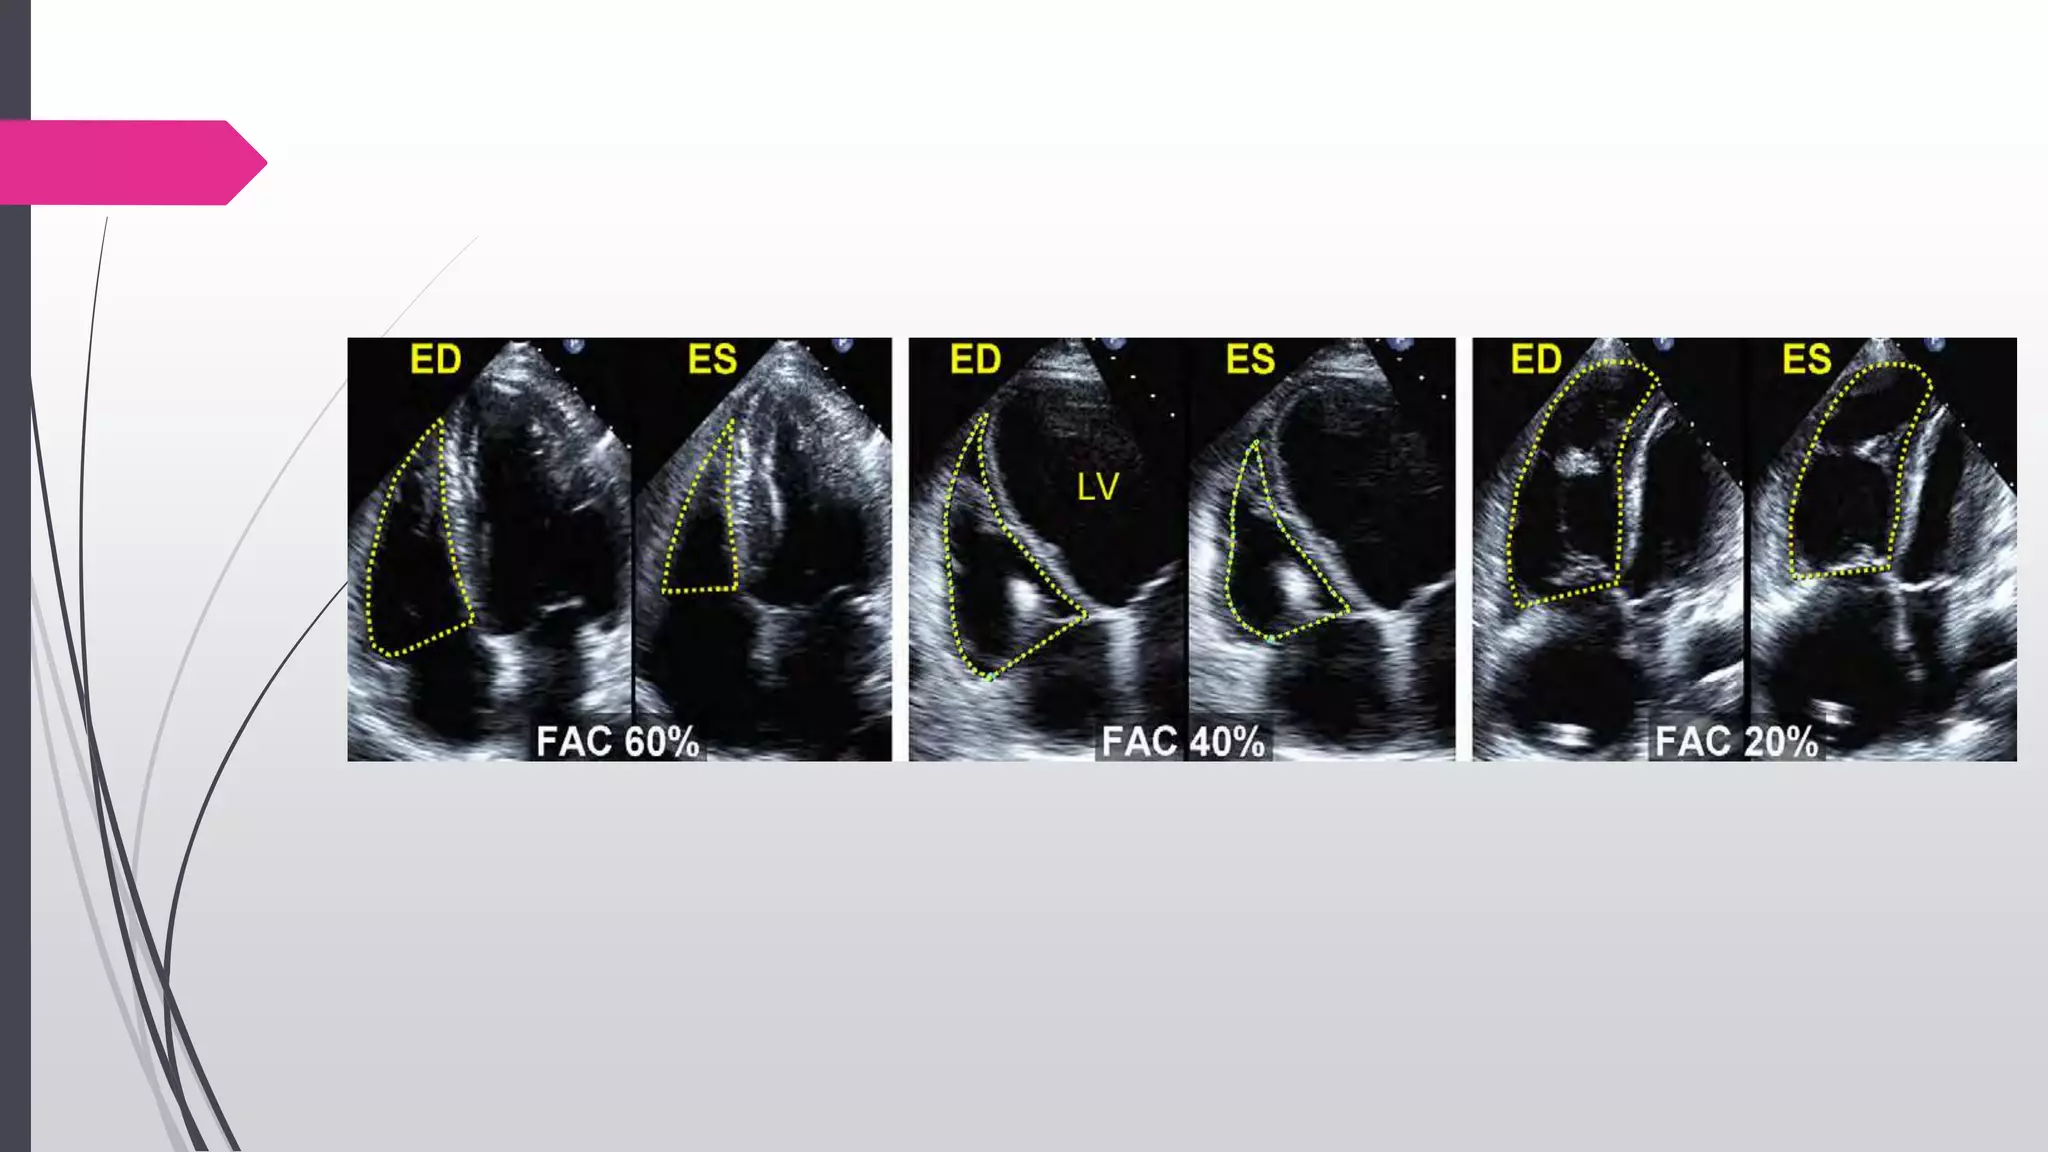

RV Area and FAC

Endocardial border is traced A4C views from the tricuspid

annulus along the free wall to the apex, then back to the

annulus, along the interventricular septum at end-

diastole (ED) and end-systole(ES).

Trabeculation, tricuspid leaflets, and chords are included

in the chamber.

 Normal FAC >35%.

End diastolic area – End systolic area

100

End diastolic area